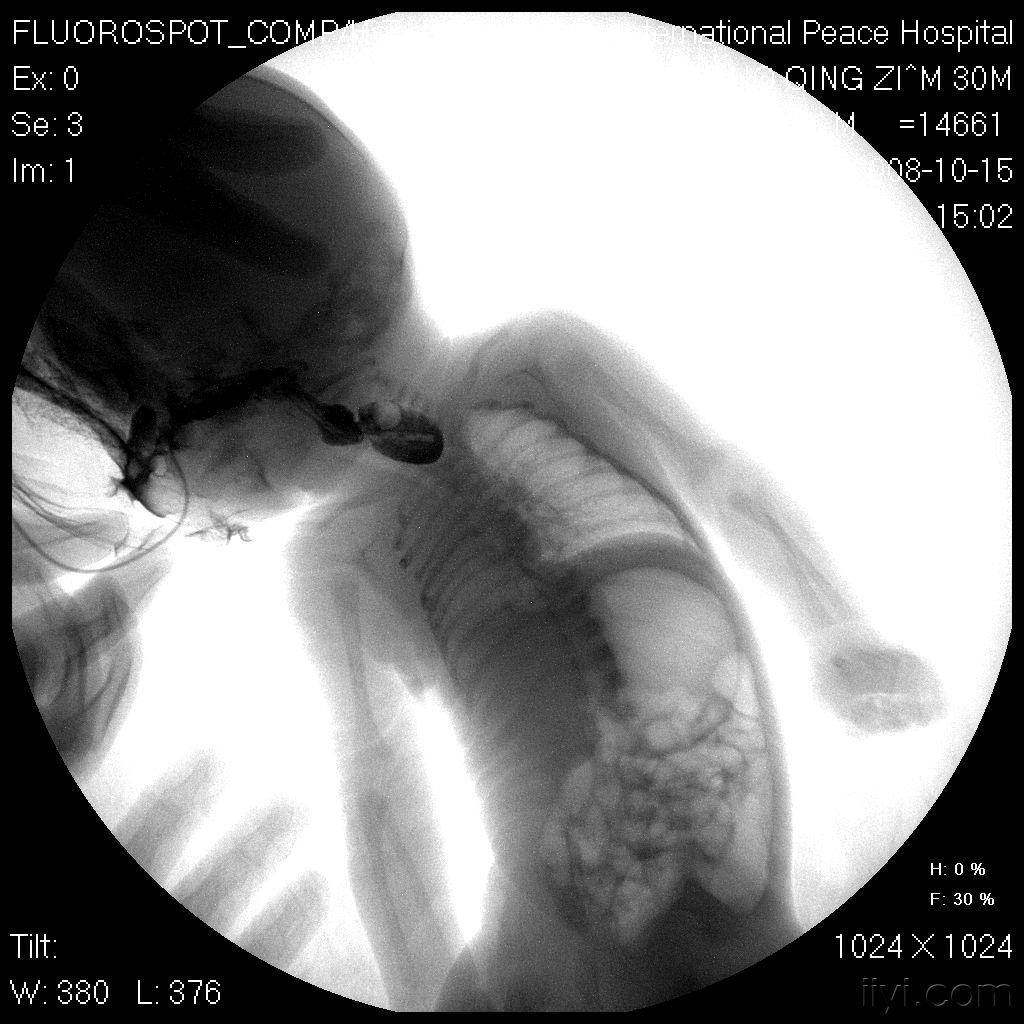

右位心CT

右位心CT,右位心CT

右位心胸片

右位心x线

镜面右位心

右位心x线表现

右位心图片

右位心解剖图

右位心影像图片